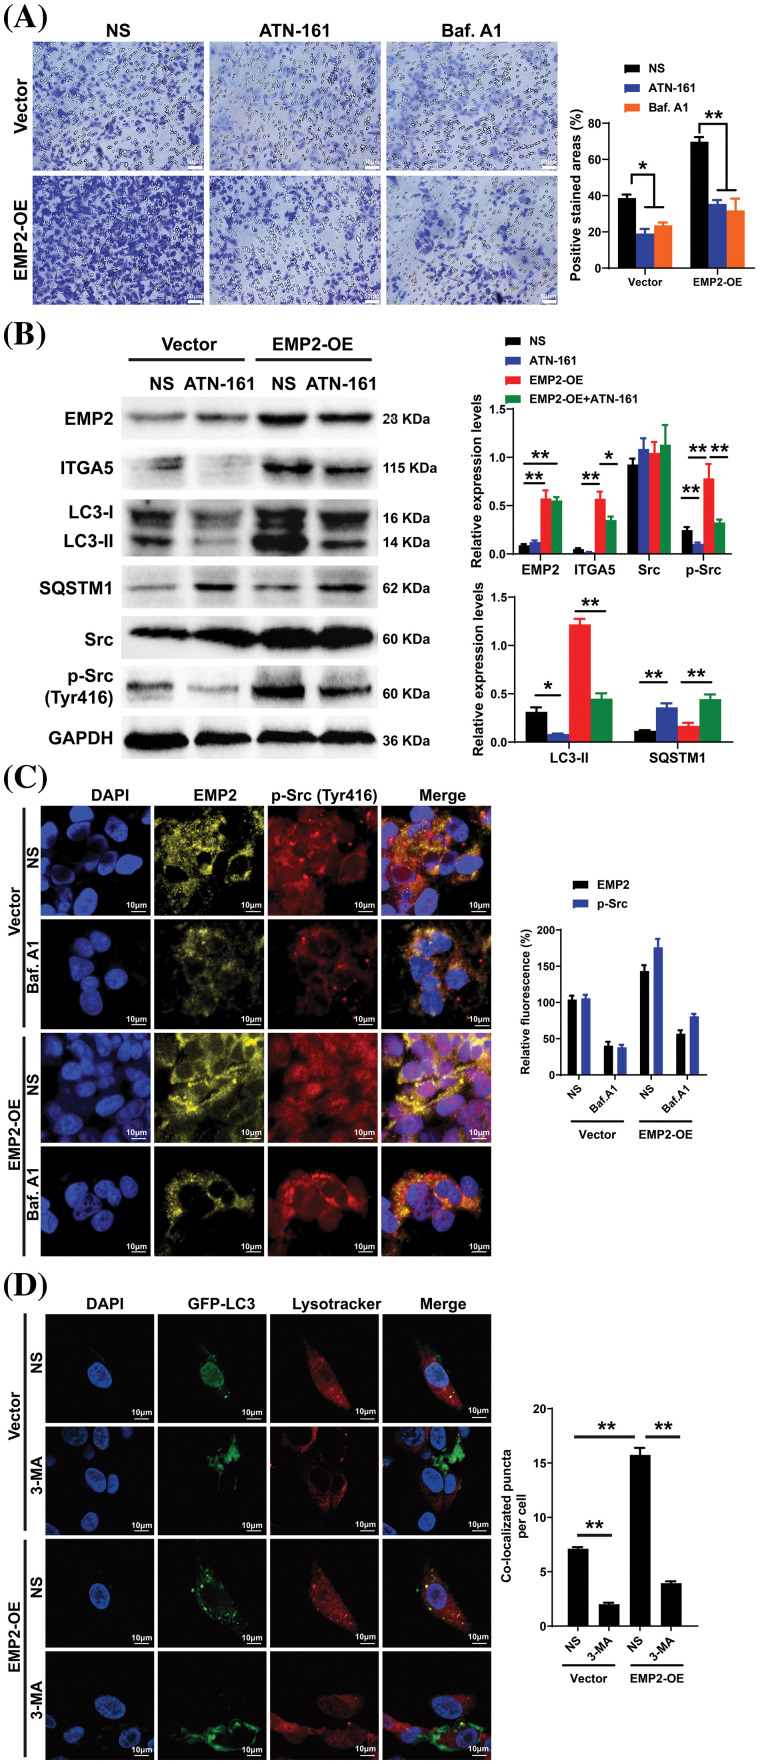

To further elucidate the correlation between EMP2, autophagy, and integrins in HCC, ATN-161, bafilomycin A1 (Baf.A1), and 3-methyladenine (3-MA) were added to HepG2 cells overexpressing EMP2, and the changes in cellular invasion capacities and their effects on related proteins were observed. ATN-161, an integrin inhibitor, has demonstrated anti-tumor efficacy in advanced solid tumors [ref. 38]. Baf.A1 and 3-MA are potent inhibitors of autophagy [ref. 39,ref. 40]. As illustrated in Fig. 7A, both ATN-161 and Baf.A1 significantly inhibit the invasive capacity of HepG2 cells in the extracellular matrix. Furthermore, EMP2 overexpression substantially enhances the invasive ability of HepG2 cells, resulting in a significant increase in the number of transmembrane cells. However, the addition of ATN-161 and Baf.A1 significantly suppresses the promoting effect of EMP2 on the invasive ability of HepG2 cells. These findings indicate that the invasive process regulated by EMP2 is influenced by both integrin and autophagy. Integrins and EMP2 are transmembrane proteins situated on the cell surface [ref. 10]. Previous studies have demonstrated a direct interaction between integrins and EMP2, with both being involved in various physiological and biochemical processes, such as cell proliferation and signaling [ref. 10,ref. 14]. When engaged in regulating cellular processes, integrins can activate multiple signaling molecules, such as Src, recruit kinase complexes, phosphorylate downstream signaling molecules, activate cell signaling pathways, and regulate tumor cell growth and metabolism, thereby influencing tumor development [ref. 41,ref. 42]. Fig. 7B illustrates that in the empty vector control group, the expression of EMP2 and p-Src is significantly inhibited by ATN-161. In contrast, the addition of ATN-161 suppresses the increased expression of EMP2 and p-Src caused by EMP2 overexpression in the EMP2 overexpression group. Moreover, the evident co-localization of EMP2 and p-Src suggests a direct interaction. These findings indicate that the expression of EMP2 and p-Src, as well as their interaction, are partially regulated by autophagy. As shown in Fig. 7C, the expression of EMP2 and p-Src was significantly inhibited by Baf.A1 in the empty vector control group. However, the addition of Baf.A1 suppresses the increased expression of EMP2 and p-Src caused by EMP2 overexpression in the EMP2 overexpression group (Fig. 7C). Furthermore, EMP2 and p-Src exhibit a certain degree of co-localization, suggesting a possible direct interaction between the two. These results suggest that the expression of EMP2 and p-Src, as well as their interaction, are partially regulated by autophagy. Fig. 7D illustrates that GFP-LC3 was transiently transfected into HepG2 cells of different groups, and the lysosome probe Lysotracker was added to observe the effects of 3-MA and different EMP2 expression states on the interaction between autophagosomes and lysosomes. The results indicate that in the EMP2 overexpression group of HepG2 cells, the number of autophagosomes and the fusion of autophagosomes with lysosomes significantly increased. The enhanced autophagy in HepG2 cells caused by EMP2 overexpression can be partially reversed by 3-MA.